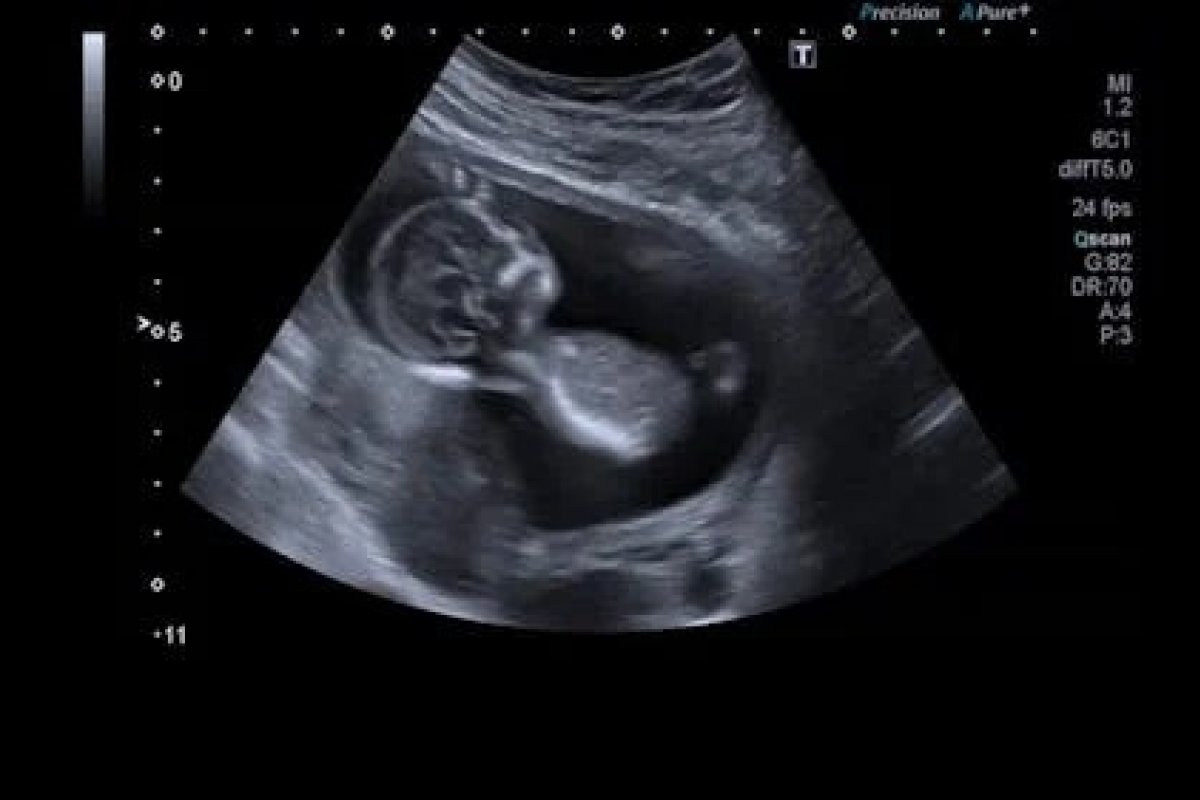

Segundo os dados do Ministério da Saúde, no período entre janeiro e maio deste anos, 31 crianças e adolescentes entre 8 e 14 anos se tornaram "mães" por dia no Brasil. Além disso, três adolescentes de 14 a 17 anos morreram durante o parto. A média é resultado de 4.657 nascidos vivos no país dentro dessa faixa etária.

Em relação a 2023, o número indicou uma queda de 23%, nos bebês nascidos de crianças e adolescentes de 8 a 14 anos, cerca de 6.080 os registrados. As maiores taxas foram nas regiões Nordeste, Sudeste e Norte.

Ao todo, 6.118.205 bebês nasceram de meninas adolescentes no Brasil em 17 anos, conforme uma pesquisa feita pelo Instituto de Saúde Coletiva da UFBA (Universidade Federal da Bahia) e Centro de Integração de Dados e Conhecimentos para Saúde da Fiocruz. Entre meninas indígenas, de 10 a 14 anos, o número de partos chega a ser quatro vezes maior.